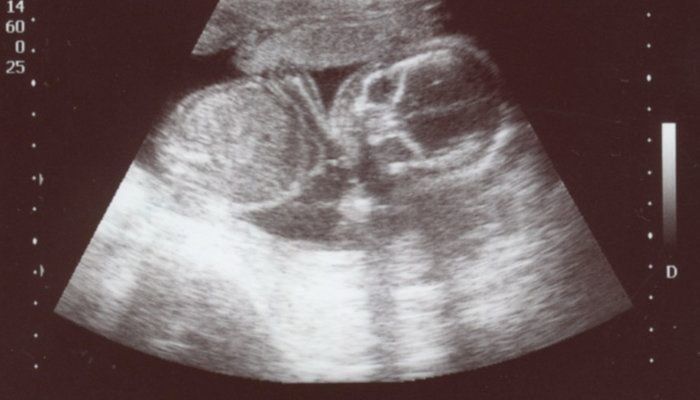

かえるさんの妊娠18週目のエコー写真

頭がくっきり。そして足を曲げている様子もわかります。5カ月目に入り、ようやくつわりがおさまりました。早速、やりたかったマタニティーヨガに挑戦。結果は、お香の匂いと逆転のポーズで吐いてしまいました。ちょっと調子に乗りすぎたようです。でも、ちょうど紅葉の季節にさしかかり、一泊旅行に出かけるなど楽しいことがたくさんできました。